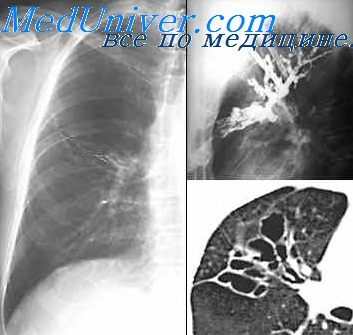

В клинике общей хирургии I ММИ им. И. М. Сеченова Л. М. Недвецкая (1963) выполнила контрастное исследование бронхов у 26 больных с продолжающимся кровохарканьем и через 4—50 часов после массивного кровотечения. В подобных случаях в рентгеновском кабинете устанавливалась система для переливания крови на случай возникновения или усиления кровотечения, а операционная заранее готовилась к возможности производства экстренной операции.

Опыт показал, что проведенные при продолжающемся кровохарканье и непосредственно после кровотечения бронхографии не вызвали усиления кровотечения и в ряде случаев позволили уточнить локализацию и распространенность поражения, благодаря чему оказалось возможным оперировать больных в ранние сроки.

Таким образом, следует считать, что при легочных кровотечениях контрастное рентгенологическое исследование должно осуществляться по прошествии нескольких дней после прекращения кровотечения, но при наличии показаний к экстренной операции и отсутствии данных о локализации и распространенности патологического процесса, вызвавшего кровотечение, бронхография может быть произведена непосредственно после остановки кровотечения или при продолжающемся кровохарканье с условием обязательного применения активной гемостатической терапии и подготовки операционной к экстренной операции.